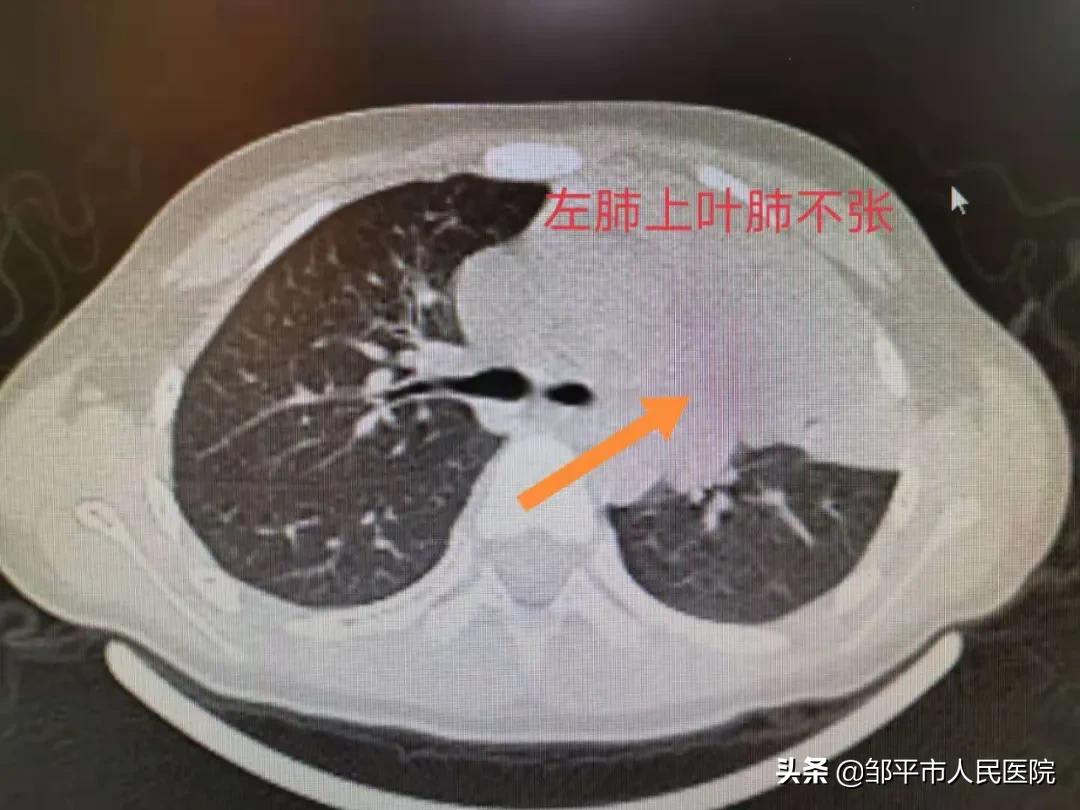

几天后,孩子体温再次升高,最高体温接近40度,咳嗽加重伴咳痰,不易咳出,患儿精神饮食差,入院检查为重症肺炎合并肺不张。

检查显示为重症肺炎合并肺不张

重症肺炎合并肺不张是比较严重的肺部疾病,单纯输液治疗效果差,有永久气道闭塞的风险,肺泡灌洗术是目前治疗重症肺炎伴肺不张最有效的诊疗技术。儿二科团队一面为患儿进行抗感染治疗,一面准备行支气管肺泡灌洗术。